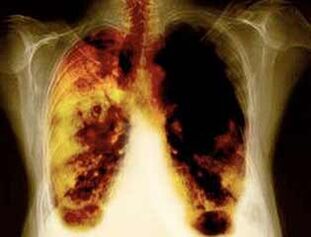

- Redución do risco de desenvolver cancro de pulmón e moitos outros tipos de cancro.

- Redución do risco para desenvolver certas enfermidades pulmonares (por exemplo, enfermidades pulmonares obstructivas crónicas).

- Despois de 1-9 meses, prodúcese tose e falta de respiración: Zil (pelo pequeno) normalmente comeza a tratar o moco, para limpar os pulmóns e reducir o risco de infección.

- 10 anos despois de fumar un 40%, a probabilidade de cancro de pulmón diminúe un 40%.